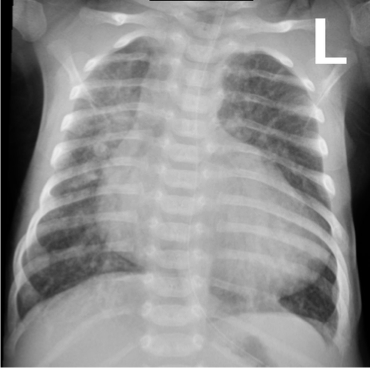

- CXR may suggest lung disease particularly if the findings are asymmetrical.

- If the changes are diffuse and symmetric, i.e., compatible with pulmonary edema or increased PVM, it is difficult to differentiate between primary lung disease or heart disease causing pulmonary edema, e.g., TAPVD with obstruction.

- A chest radiograph: cardiomegaly, narrow mediastinum, and increased pulmonary vasculature. ECG: RAD and RVH

Imaging

- Small to N cardiac silhouette

- Decrease pulmonary vasculature